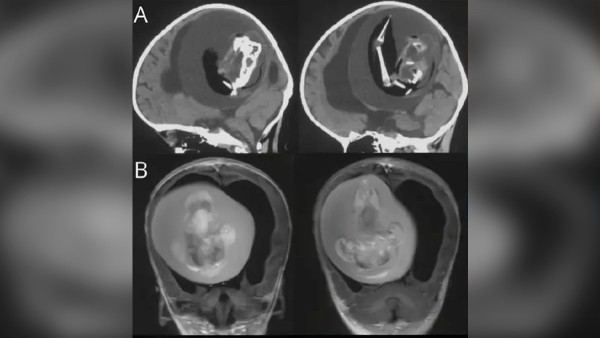

Los médicos realizaron una tomografía computarizada de la cabeza de la niña, descubriendo una masa de 13 centímetros.

Al realizarse la intervención quirúrgica, se pudo observar que el feto del "gemelo parásito” mostraba indicios claros de desarrollo: columna vertebral, dos huesos de la pierna (fémur y tibia), además de dedos en las extremidades superiores. Además, se identificó que sufría de espalda bífida (cuando parte de la médula espinal queda expuesta).

Pruebas de ADN confirmaron que se trataba del gemelo de la niña, el cual había continuado creciendo a partir del suministro de sangre por parte de su hermana.

La compresión del tejido cerebral causada por el feto dentro del cráneo de la bebé fue severa. A pesar de la intervención quirúrgica, la niña nunca pudo despertar de la operación y permaneció conectada a un respirador durante 15 días antes de fallecer debido al daño cerebral irreversible.